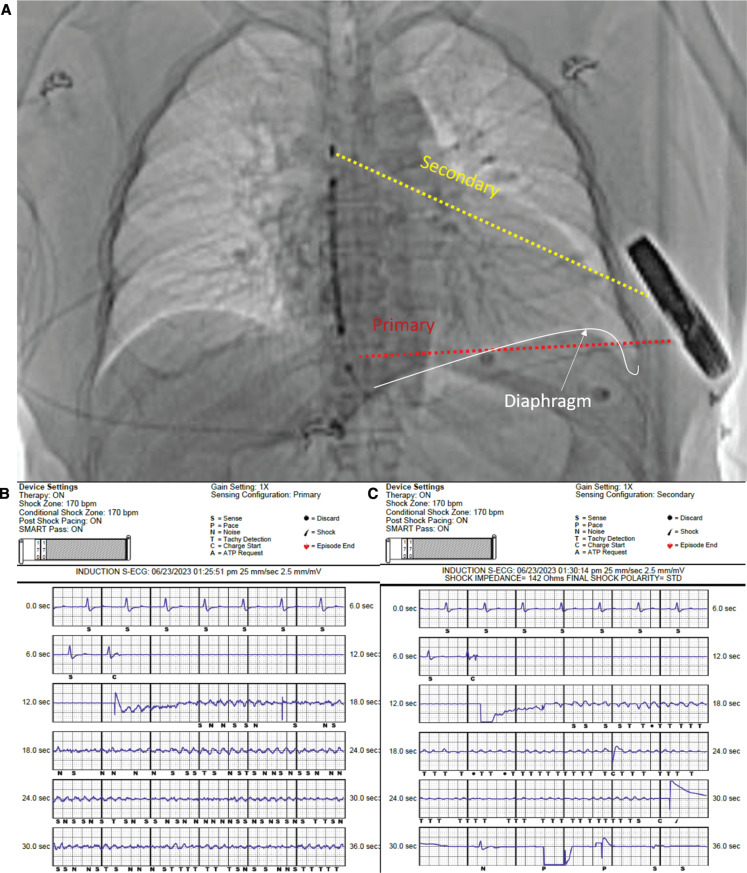

Oversensing of extra-cardiac noise may inhibit delivery of subcutaneous cardiac implantable defibrillator (S-ICD) therapy. We report a case of diaphragmatic tetany resulting in the inhibition of S-ICD therapy at the time of defibrillator testing without the use of muscle relaxants. Clinicians should be aware of this phenomenon.